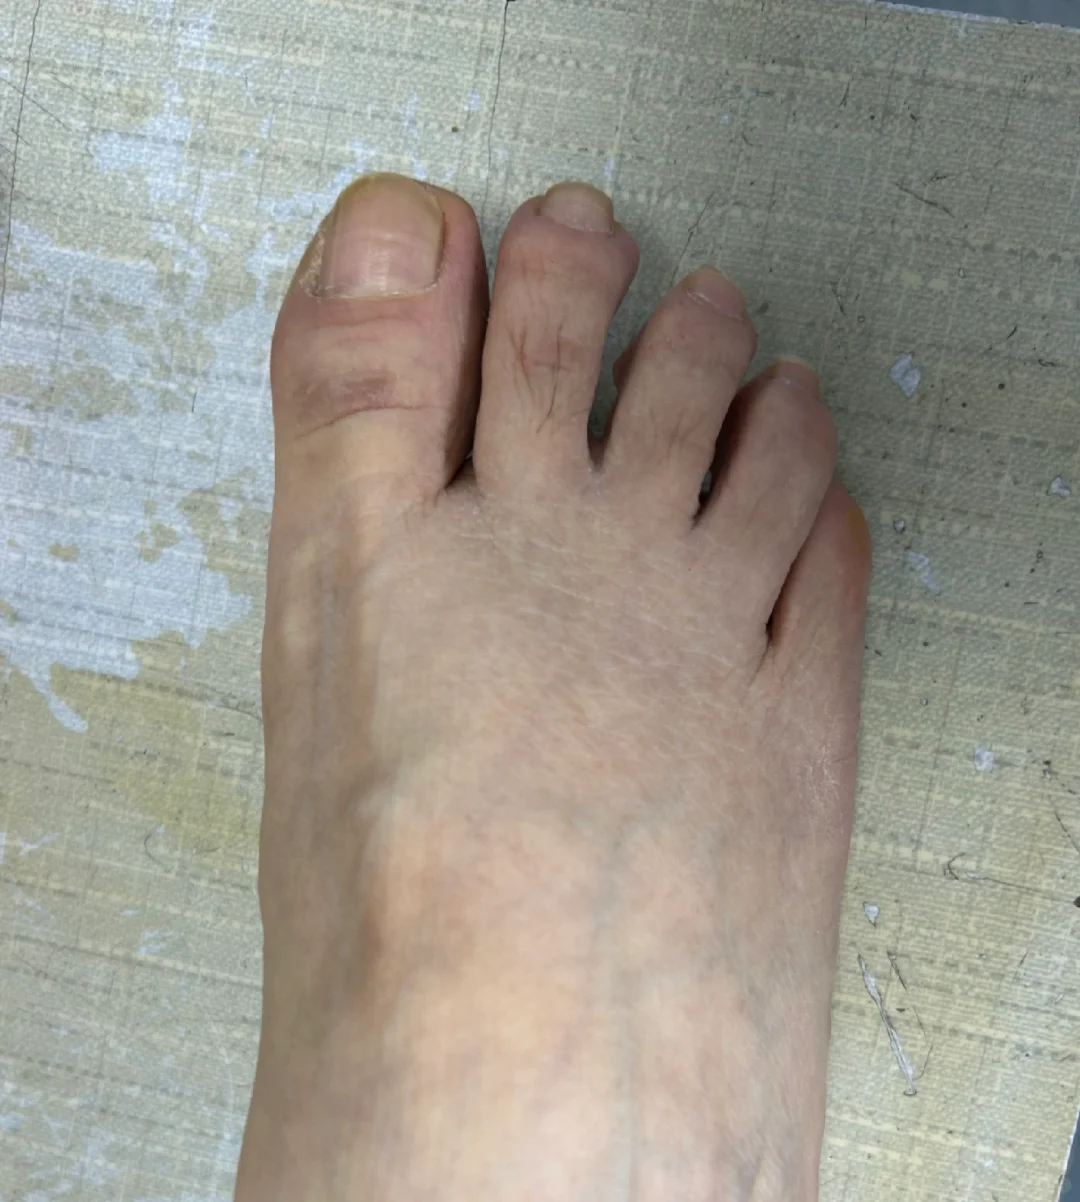

拇外翻术后三年半

手术伤口瘢痕变成白色,术后半年隆起,一年内色深,等2年后慢慢变白。 即使当初缝合愈合并没有那么好,当初没有全部内缝,还有部分外缝的蜈蚣瘢 关节稳定,匹配良好,无不适,没有复发可能 片子上缺损的三角骨区域长满新骨,骨痂下成骨不需要担心。 新骨密度高,都是气质骨,所以强度远高于术前